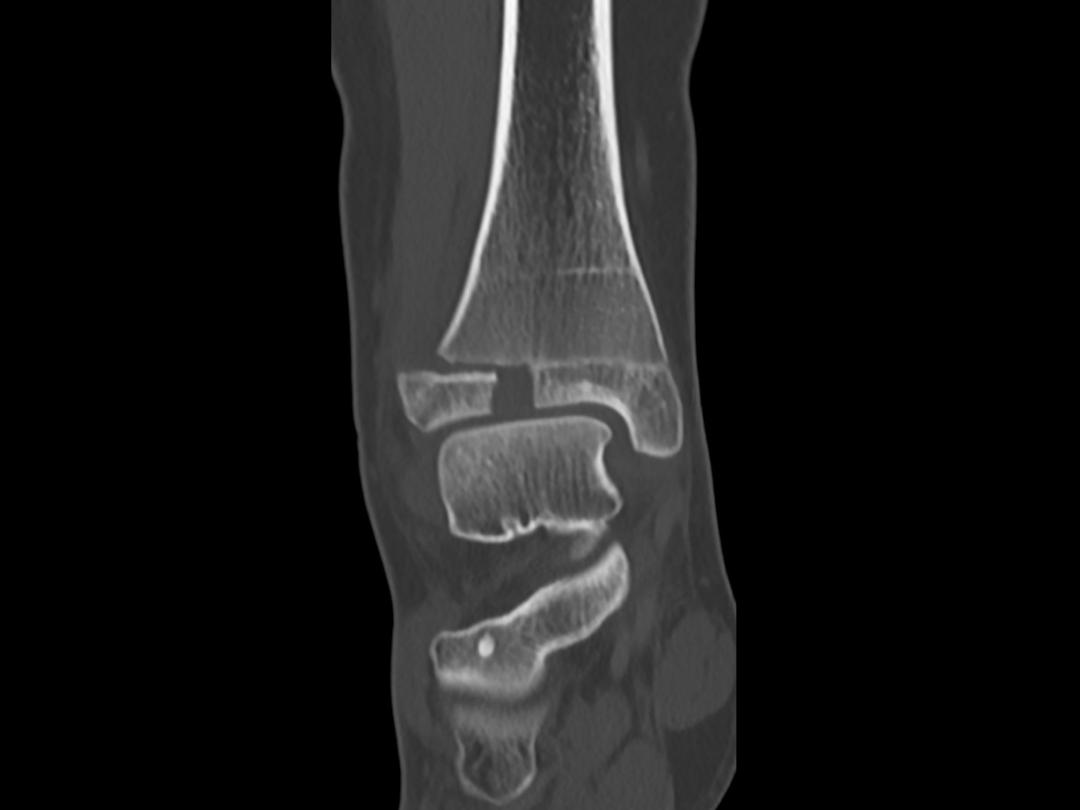

Een 13-jarig meisje kwam op de polikliniek Traumachirurgie vanwege een pijnlijke rechter enkel. Eerder die dag had ze de enkel verzwikt. Sindsdien kon ze de rechter voet niet meer belasten. Bij lichamelijk onderzoek was er sprake van zwelling en drukpijn aan de anterolaterale zijde van het enkelgewricht. Een röntgenfoto van de enkel liet een fractuur zien door de groeischijf van de distale tibia waarbij de epifyse naar anterolateraal was verplaatst (figuur a en supplement 1). Een aanvullende CT-scan van de enkel liet een Salter-Harris-type-III-fractuur zien; het gewrichtsoppervlak had een onderbreking van 8 mm (figuur b en supplement 2). Dit type fractuur wordt een Tillaux-fractuur genoemd. Wij behandelden de patiënte operatief met een open repositie en schroeffixatie (supplement 3 en 4).

Een Tillaux-fractuur is een relatief zeldzame enkelfractuur die voorkomt bij kinderen van 12-14 jaar. In deze leeftijdsperiode sluit de groeischijf van de distale tibia gefaseerd…